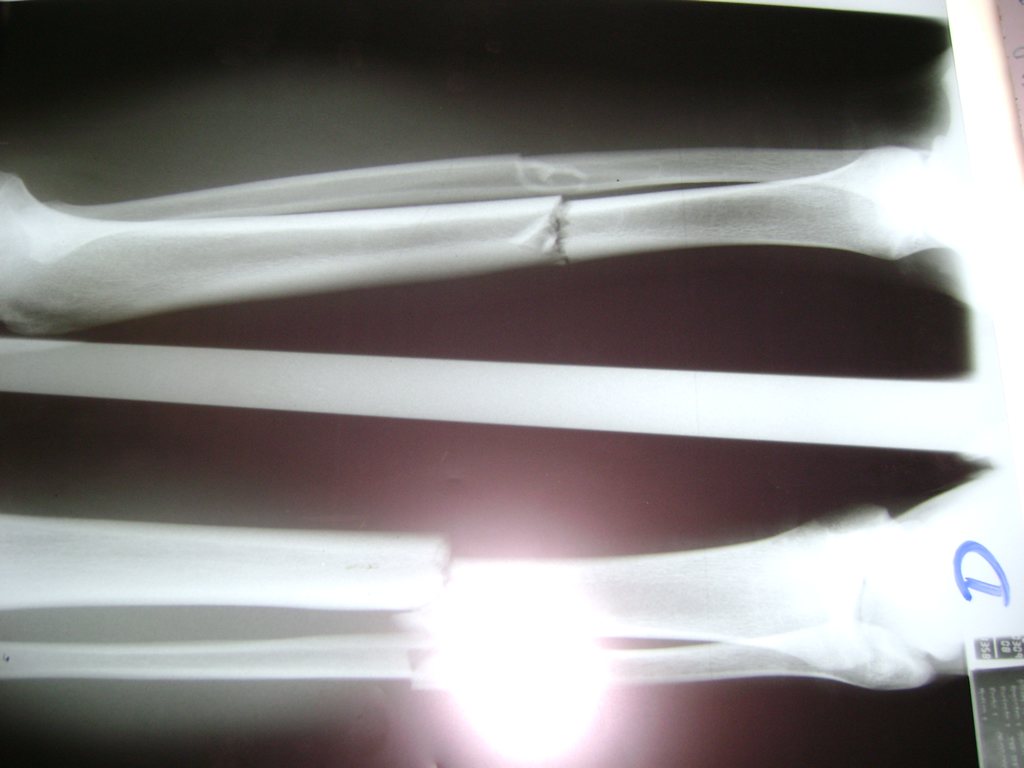

Cirugías de Calcaneo - Perone y Tibia

Aunque cada uno de estos huesos puede fracturarse por separado, normalmente la rotura es una lesión que se produce de forma conjunta

La mayor parte de las roturas implican a la parte proximal del hueso (parte del hueso próximo a la rodilla) o a la parte distal (parte del hueso cerca del tobillo).

Debido a la fina cobertura de piel que recubre la tibia y el peroné, las fracturas generalmente son abiertas, es decir, el hueso roto rasga la piel, atravesándola. Las fracturas de tibia y peroné generalmente se producen por un fuerte impacto o torsión.